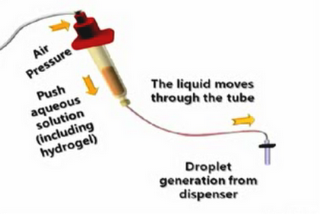

3D Tissue Printer Video

We bumped into a rather interesting video explaining and actually showing the process of using a 3D printer to deposit live cells! The video explains the main issue with tissue deposition: lack of a scaffold causes the deposited cells to lack structural integrity; they flop all over. The 3D printer enables them to… Continue reading 3D Tissue Printer Video